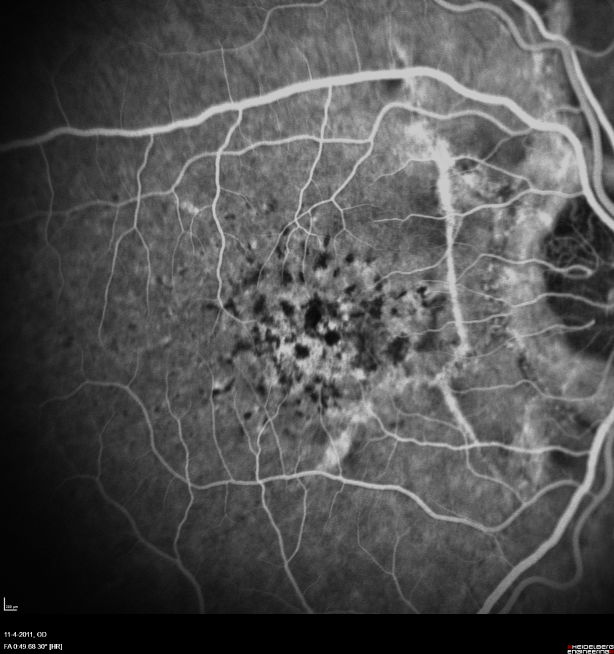

In 1989, a 21-year-old male experienced visual loss after diving from a diving board. Ocular examination was performed the same day, and revealed bilateral subretinal hemorrhages and angioid streaks. After clearing of the hemorrhages, more breaks of Bruch’s membrane were identified. The macula was not affected and vision returned to normal in both eyes. Twenty years later, in April 2009, he presented again because of recent visual loss in the left eye. Visual acuity (VA) was 20/25 in the right eye (RE) and 20/40 in the left eye (LE). Clinical examination, FA, and OCT revealed active choroidal neovascularisation nasal to the fovea with leakage and edema. One month after a first intravitreal injection of bevacizumab, the edema had resolved and vision improved. Close follow-up with consideration of additional anti-VEGF injections was adviced. Moreover, we observed in both eyes angioid streaks, peau d’orange and a few comet tails, and made a tentative diagnosis of PXE. We identified the sequellae of diving induced breaks of Bruchs’ membrane with linear vertical break formation, different from the irregular course and spiderweb configuration of the angioid streaks. During the following months a total of 8 injections of bevacizumab were administred on the LE and despite this treatment growth of the choroidal neovascularization (CNV) was observed with further deterioration of vision. In January 2010, active CNV was also identified in the right eye and treatment with bevacizumab intravitreal injections was initiated. At last examination, in April 2011, VA was 20/60 in the right eye and 20/250 in the left eye, with in the left eye a large subfoveal CNV expanding on both sides of the fovea, and in the RE a smaller and mildly active subfoveal CNV requiring further treatment (Figure 1 [Fig. 1], Figure 2 [Fig. 2], Figure 3 [Fig. 3], Figure 4 [Fig. 4], Figure 5 [Fig. 5], Figure 6 [Fig. 6], Figure 7 [Fig. 7], Figure 8 [Fig. 8], Figure 9 [Fig. 9], Figure 10 [Fig. 10]).

The characteristic ocular findings are peau d’orange, angioid streaks, and comet tail atrophic lesions. In the eyes, the first visible changes are pigment irregularities giving the fundus a peau d’orange-aspect, most visible temporal to the fovea. This typically precedes the appearance of angioid streaks by several years [11]. Comet tails are pathognomonic PXE-related lesions, without functional repercussion, appearing later in the disease [2]. Angioid streaks are not pathognomonic for PXE, although PXE is the most common associated systemic disorder. Angioid streaks have been described in a variety of other systemic disorders including Ehlers-Danlos syndrome, Paget’s disease, Marfan’s syndrome, sickle cell anaemia, thalassaemia and acromegaly and in these systemic diseases other characteristic findings may lead to identification of the angioid streaks-associated disease. On the other hand, angioid streaks are observed in at least 85% of PXE patients. They are disease-induced breaks of Bruchs’ membrane and remain asymptomatic, unless the macula is affected. In patients with skin lesions, fundus screening usually reveals angioid streaks as early as at age 15 and occasionally earlier [1]. Vision loss occurs in the majority of patients with PXE by the age of 50 because of macular or paramacular angioid streaks-associated ruptures in Bruchs’ membrane and choroidal neovascularization causing retinal oedema, hemorrhages and scar formation. Till recently, the prognosis of PXE-associated CNV was extremely poor, but intravitreal injections with bevacizumab and ranibizumab have improved the prognosis and are able to stabilize or even improve vision in patients with recent loss of vision due to CNV [12], [13]. Other causes of visual loss in PXE are macular atrophy, generalized retinal dysfunction and optic nerve head drusen with associated nerve fiber loss [14].